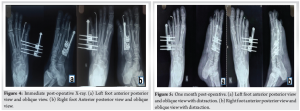

Under sterile aseptic precautions, under spinal and epidural anesthesia, the patient was positioned supine, and the parts were painted and draped. Skin markings for the extent of the fourth metatarsal were made under an image intensifier (Fig. 3a). A K-wire was passed into the fourth toe to immobilize the MTPJ to prevent dislocation (Fig. 3a, b, c, d, e)[13]. A 4cm skin incision was made along the fourth metatarsal extent (Fig. 3b). Subcutaneous tissue was cut and retracted. The extensor digitorum longus tendon was visualized and retracted. Four Schanz pins of size 2.5 mm were inserted (two proximally and two distally) (Fig. 3b). An osteotomy was performed after the circumferential drilling of the metatarsal shaft with a 1.5 mm K-wire with one entry and three exits. The external fixator was attached to the Schanz pins (Fig. 3c). Skin was closed in layers, and a sterile dressing was applied[14].

Post-operatively Immediate post op Xray taken followed by(Fig 4a,b) management with analgesics and antibiotics was started. Pin sites were regularly dressed to prevent post-operative infections. The patient was advised to be strictly non-weight bearing after surgery. Ten days post-operatively, the patient was given time for soft tissue healing and swelling to reduce. Distraction of the metatarsal was started with 0.25 mm twice daily. X-rays were taken every 10 days to check for callus formation, bone alignment, and MTPJ stability(Fig 5a,b). Distraction was conducted for 40 days, with X-ray showing regeneration of 2 cm along with callus and satisfactory arch of parabola connecting all metatarsal heads (Fig. 6a, b). The external fixator was removed after 2 months (Fig. 7a, b). After the fixator was removed and time was given for the callus to gain satisfactory strength, the patient was mobilized with full weight-bearing on day eighty[15].